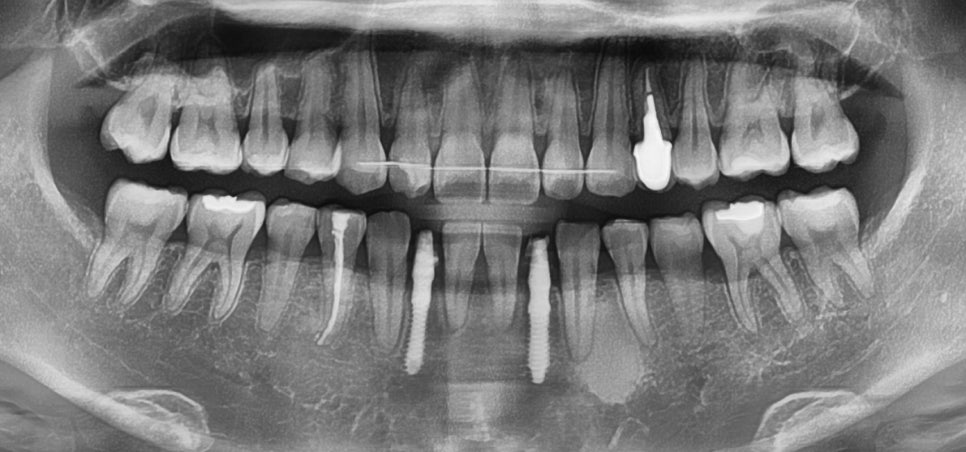

결손된 부위에 임플란트 를 심는다면

기울어지고 벌어진 이들을

올바른 위치로 이동시키고,

과도하게 맞물린 부분을

적절한 높이로 조정하는 과정이

우선되어야 됩니다.

따라서 교정 치료를 먼저 진행합니다.

이는 향후 임플란트 가 식립될 공간을 확보하고,

교정 치료가 어느 정도 진행된 단계에서

임플란트를 의뢰를 통해 식립하고,

즉시 저작 기능을 도울 수 있는

임시 치아를 제작해드립니다.

25.03.27

교정 치료가 어느 정도 진행되어

임플란트 식립에 알맞은 공간이 확보되면,

중간 단계에서 임플란트 의뢰를 통해

식립된 것을 관찰할 수 있습니다.

25.03.20

임플란트를 식립하고,

즉시 임시 치아를 제작하여

장착한 모습입니다.